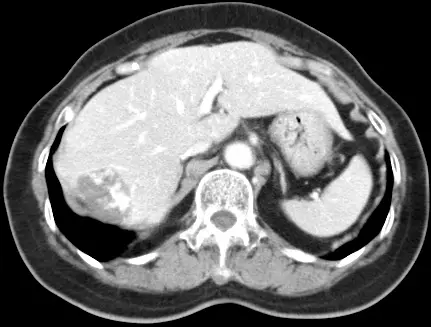

本題提供三張 Dynamic CT 影像,為肝臟右葉 4 cm 腫瘤的三期掃描:

圖三(延遲期 Delayed phase):病灶呈現幾乎完全等密度或高密度填充,與正常肝臟實質密度相近或更高,強化持續存在(persistent enhancement),無 washout 現象。

此三期「周邊結節強化 → 向心性填充 → 延遲完全填充」的模式,是海綿狀血管瘤的病理特徵性表現(pathognomonic pattern)。